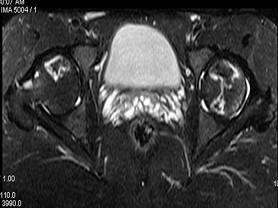

问题 患者,男,24岁,曾有外伤史,两侧髋部疼痛不适数月,请结合所提供的图像,选择最佳答案 ( )

选项 A、化脓性骨关节炎 B、类风湿关节炎两侧 C、髋关节退行性变 D、未见异常 E、股骨头无菌性坏死

答案 E